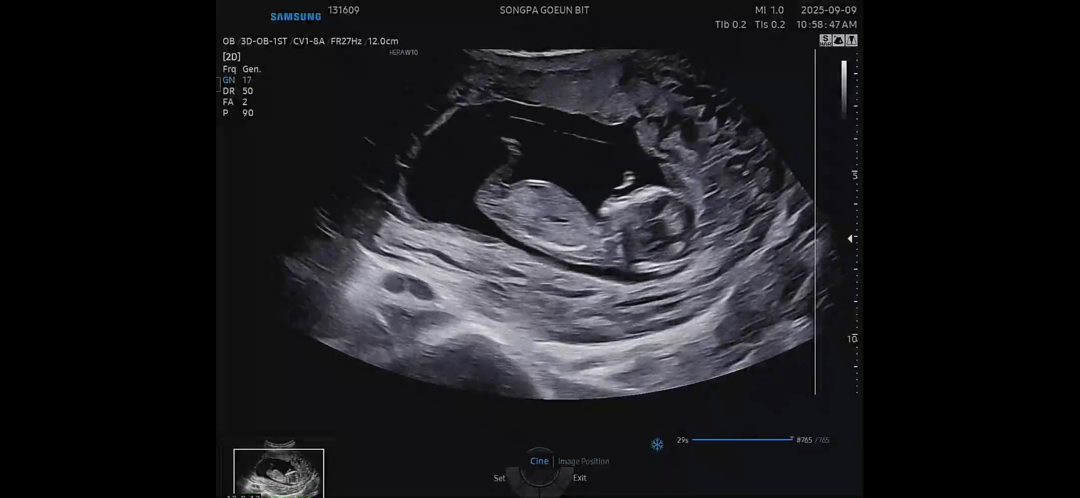

12주 각도법 예측부탁드립니다

각도법 보려고했는데 생식기처럼 톡 튀어나온사진은 없더라구요 이 사진으로 각도법 예측가능할까요